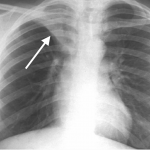

RIGHT UPPER LOBE ATELECTASIS

The archive below organizes different examples of a right upper lobe atelectasis. It will really be the anatomical location of the finding that will help diagnosis this SPECIFIC subtype of atelectasis. Click on the thumbnails below to view the archive.